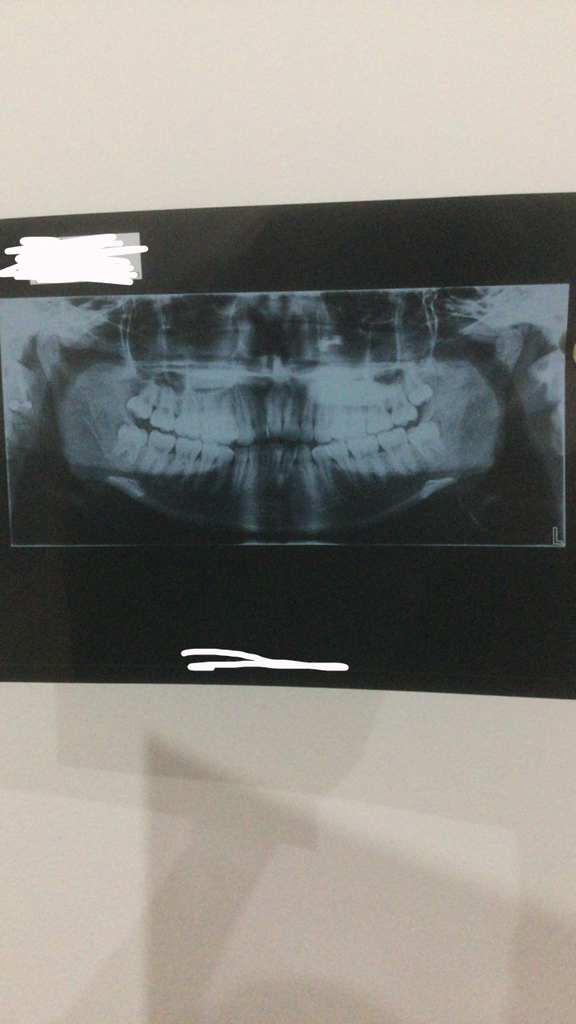

Okay so I went to my ortho today, he was looking at my teeth, said all the right things (crowding, 9mm overjet, severe class 2 malocclusion, crossbite),

Anyways I underwent an OPG and a Cenograph, these are the results.

Anyways I underwent an OPG and a Cenograph, these are the results.